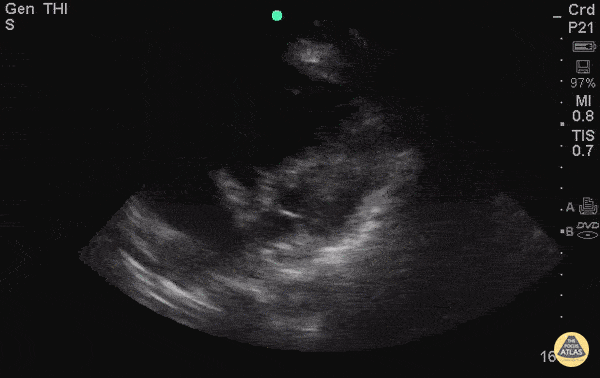

Right Ventricular Dysfunction - RA Thrombus with R Heart Strain

Middle age F presented initially to ED after a mechanical fall complaining of hip pain. Patient became tachypnic and altered during ER stay. POCUS done, and RA thrombus was noted with D sign and enlarged R ventricle. R heart thrombus (thrombus in transit) is highly mobile differentiating it from a mural thrombus, which forms in situ. A meta-analysis of 1113 patients from the International Cooperative Pulmonary Embolism Registry showed mortality was 2x as high for pts with right heart thrombus and PE compared to those without right heart thrombus. The difference in mortality was more pronounced in the heparin alone treatment group (vs. lytics or embolectomy). Another study by Rose et al (2002) showed patients with PE and a right heart thrombus had a mortality of 27%. They found these patients did better when treated more aggressively (i.e. thrombolysis or embolectomy). Rose PS, Punjabi NM, Pearse DB. Treatment of right heart thromboemboli. Chest. 2002;121(3):806-14. (PMID: 11888964) Torbicki A, GaliƩ N, Covezzoli A, et al. Right heart thrombi in pulmonary embolism: results from the International Cooperative Pulmonary Embolism Registry. J Am Coll Cardiol. 2003;41(12):2245-51. (PMID: 12821255) Submitted by Bobak Zonnoor, MD